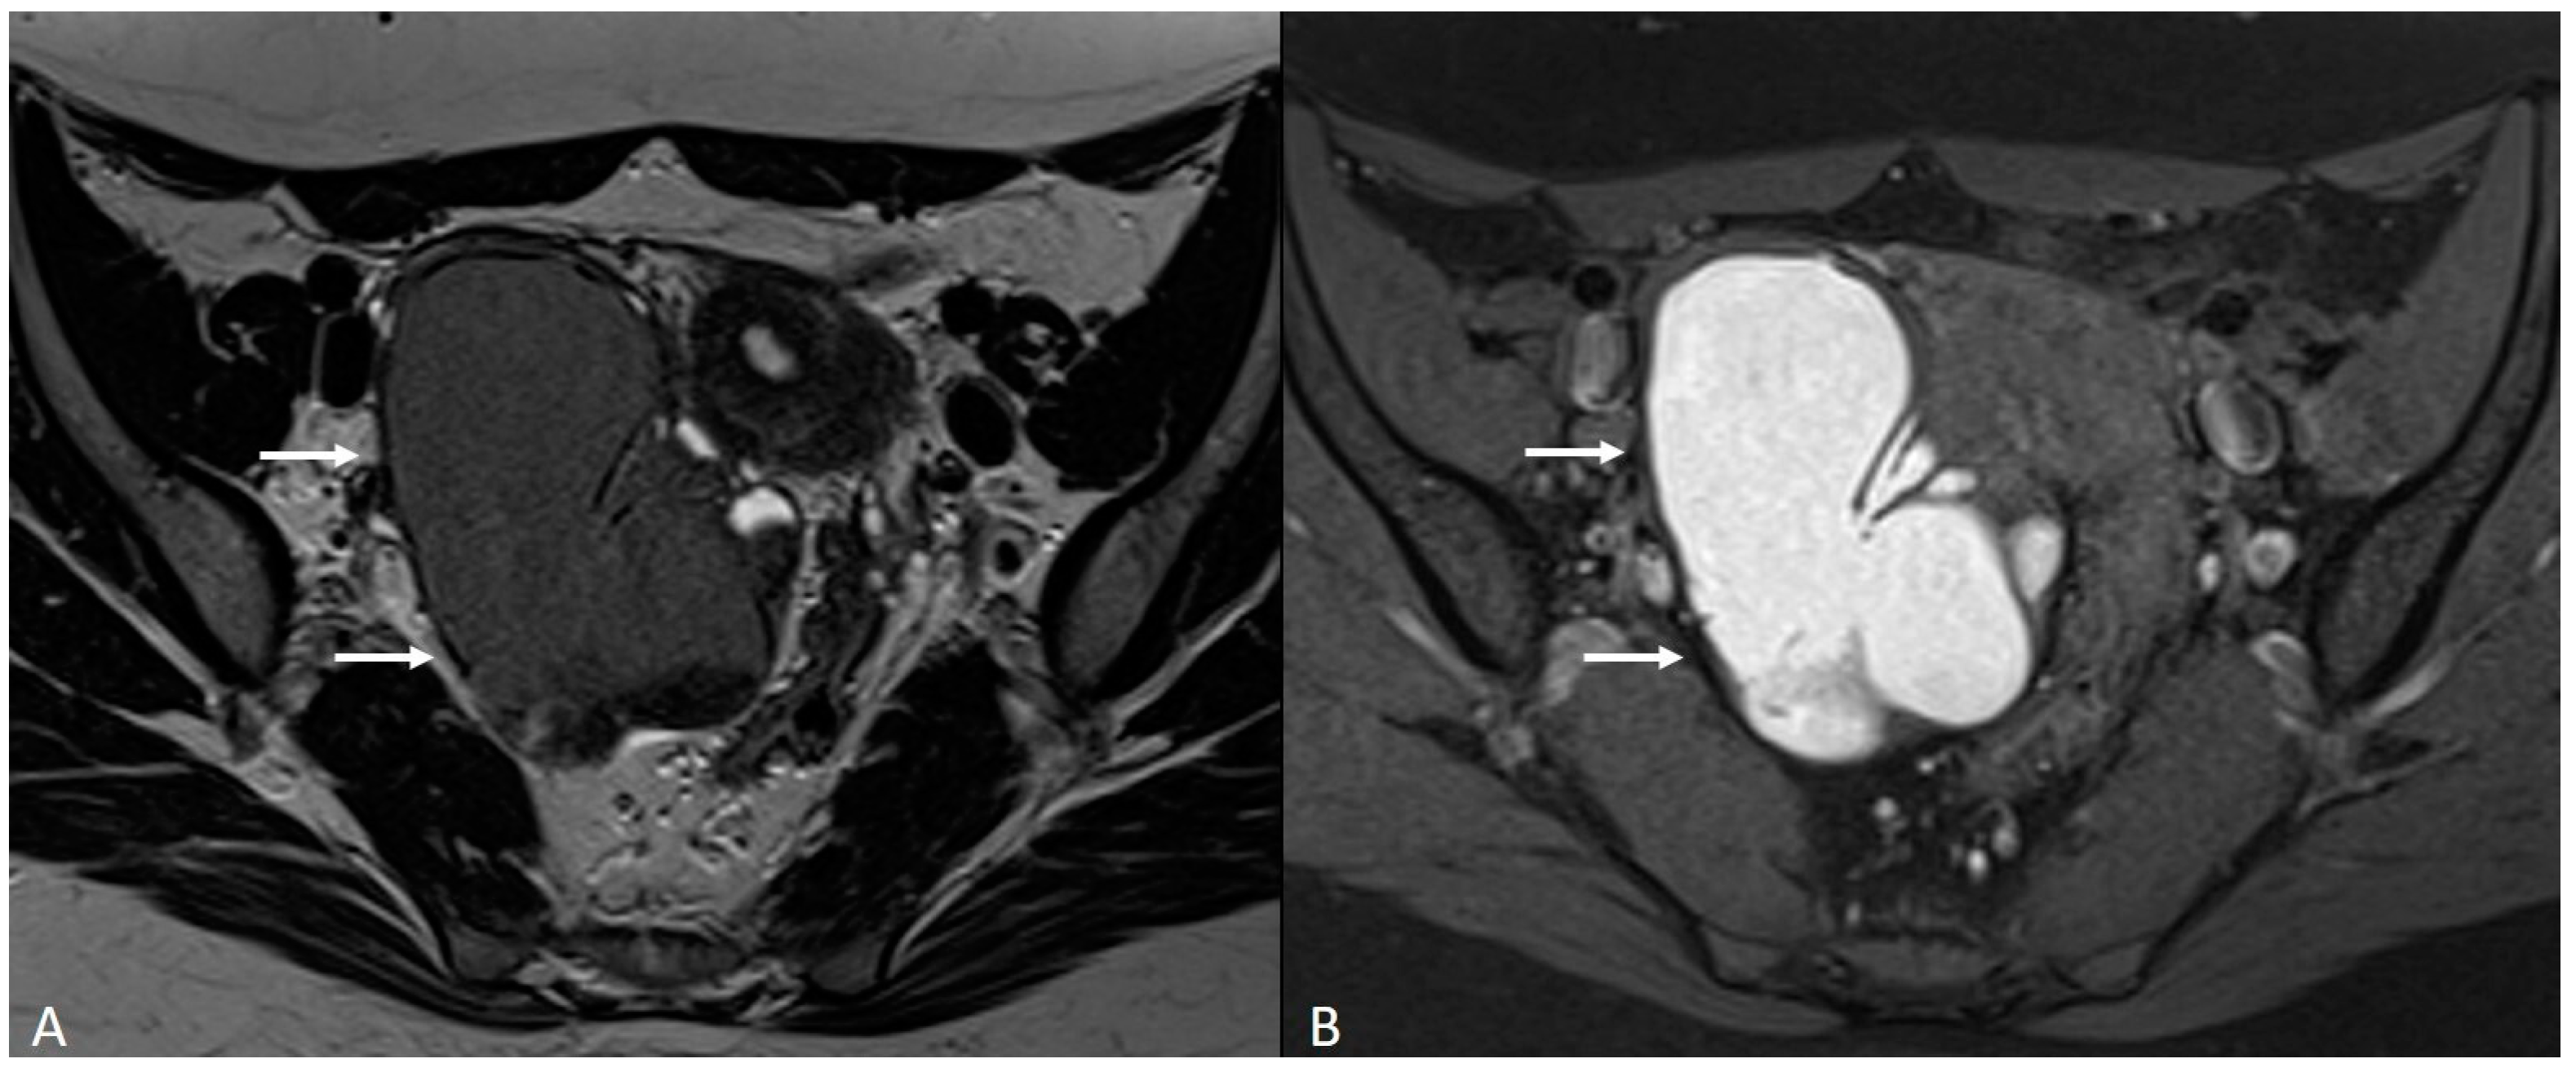

Generally, they appear hyperintense on fat-suppressed T1WI and T1WI (Figure 7 and Figure 8). The hyperintensity on fat-suppressed T1WI helps differentiate endometriomas from dermoid cyst and teratoma, which usually contain fat [51]. On T2WI, a variable signal can be obtained: a hypointense signal can affect variable portions of the cyst, sometimes also presenting a stratification, until a complete loss of the signal. This is called the shading sign and is correlated to the different state of hemoglobin degradation [52] (Figure 8). The T2 dark spot sign refers to hypointense spots in the wall of the cyst due to the presence of macrophages (Figure 9).

Figure 8.

Right tubo-ovarian endometriosis in a 25-year-old female patient with reported localized abdominal pain in the right iliac fossa, which increases intensity during the menstrual cycle. (A) Axial T2WI; (B) Axial fat-suppressed T1WI. Enlarged right adnexal cyst with incomplete septa denoting dilated tube (white arrows). The cystic content shows low signal intensity on T2WI and high signal intensity on fat-suppressed T1WI, consistent with hemorrhagic fluid.